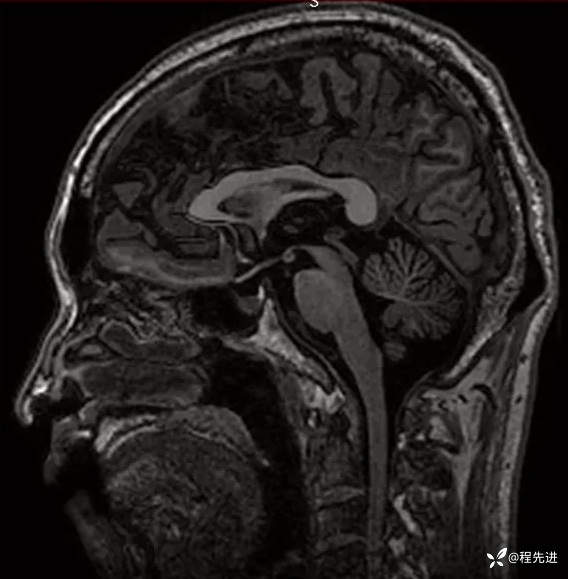

T1: